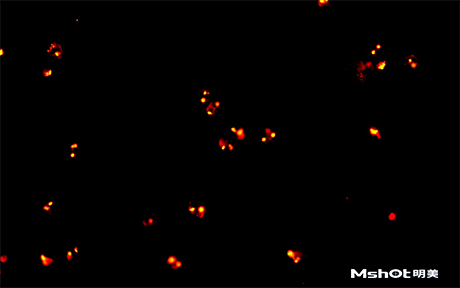

北京某試劑單位已有一臺(tái)奧林巴斯生物顯微鏡BX61,希望能進(jìn)行CTC檢測,在電腦中成像拍攝保存圖片,剛好我們在北京有辦事處,工程師了解到具體需求分析后提供一款明美數(shù)字?jǐn)z像頭MS23,搭配奧林巴斯BX61生物顯微鏡在40X觀察下,效果如圖::